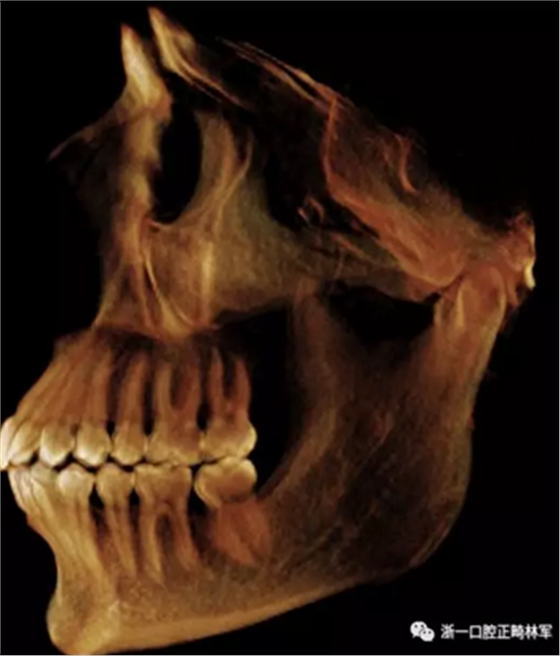

在輸出的3D模型上,使用體內(nèi)軟件(Anatomage,San Jose,Calif)將下頜骨以最小的間隔從顱骨上分離(圖5)用于保留下頜骨的咬合細(xì)節(jié),游離的下頜骨被保存(圖6,A)。同時(shí),將沒有下頜骨的顱骨導(dǎo)出并保存(圖6,B)。

圖6. A,從整個(gè)3D模型上修剪的下頜骨; B,修剪的顱骨。

使用體內(nèi)軟件,第一次融合包括咬合導(dǎo)板在下頜牙齒上定位(圖7)。 圖8顯示了咬合導(dǎo)板和下頜骨(類似咬合導(dǎo)板/游離下頜骨)的完整定位。第二次融合涉及咬合導(dǎo)板的上頜牙齒與顱骨上的的上頜牙齒的定位(圖9)。除了原始的下頜骨最小牙尖分離的3D模型(圖10)之外,這將產(chǎn)生一個(gè)構(gòu)建好的下頜骨完全咬合的3D模型。